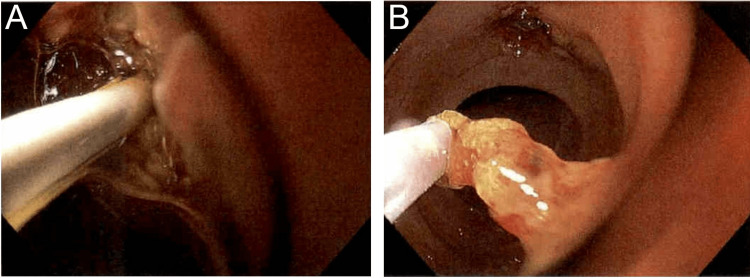

The patient was placed supine and general anesthesia was employed. A duodenoscope (EVIS EXERA II, TJF-Q190V, Olympus, Center Valley, USA) was inserted without difficulty into the stomach, at which point it became apparent the patient had had an antrectomy with Billroth II anastomosis. The efferent and afferent limbs were not easily differentiated. Each limb was explored with the duodenoscope, but due to angulation, the scope could not accurately identify the ampulla of Vater. A gastroscope (EVIS EXERA III GIF-HQ190, Olympus, Center Valley, USA) was then used to identify the afferent limb. There was initial difficulty with advancing the scope into the afferent limb, but eventually, the duodenal stump was reached and the ampulla was identified (Figure 2A). The ampulla was cannulated with a wire and a Hydratome RX 44 sphincterotome (.035"/260cm, Boston Scientific, Marlborough, USA) was advanced into the duct. A cholangiogram showed a 1.0 x 0.5 cm distal stone but otherwise normal ductal anatomy (Figure 2B–2C). A sphincterotomy was performed at approximately the 6 o’clock position accounting for the patient’s supine positioning (Figure 3A). Next, we attempted to advance an Extractor Pro RX Triple-lumen Retrieval Balloon (Boston Scientific, Marlborough, USA) over the guidewire; however, it was too thick for the channel of the gastroscope. The wire from a Jagtome Revolution RX 39 sphincterotome (.025”/260cm, Boston Scientific, Marlborough, USA) was used to cannulate the duct. As this wire had a smaller diameter, the retrieval balloon was able to be threaded over this wire and through the gastroscope channel. Some debris was removed, but the filling defect persisted. The balloon and wire were removed, and a FlowerBasket stone retrieval basket (8 WIRE, 190cm X 20mm, Olympus, Center Valley, USA) was advanced into the duct (Figure 2D). We were able to fragment the stone and witness its removal (Figure 3B). We removed the remaining debris with the balloon and performed a balloon occlusion cholangiogram which showed no filling defect (Figure 2E).